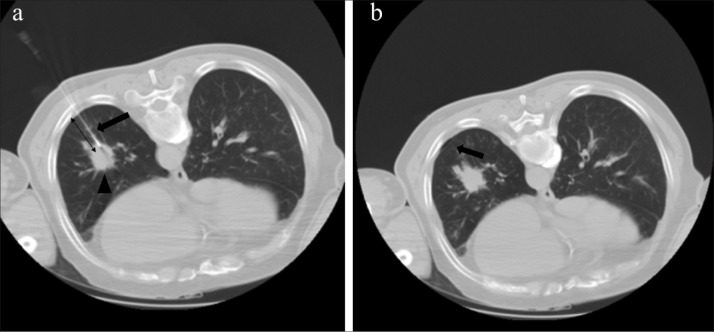

Abstract Image